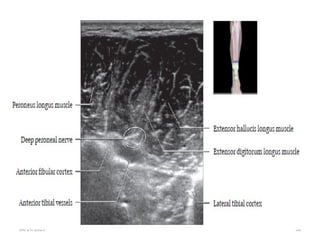

 Ultrasound

 Use high-frequency transducers to assess nerves.

 Short axis: A typical “honeycomb” appearance with hypoechoic

fascicles and surrounding echogenic perineurium

 Long axis: Parallel hypoechoic tracts of uniform caliber.

 Distortion of this uniform appearance suggests pathology

04/29/2025 42

• Trace medium-sized nerves by following their course as they

branch from their parent.

• Small (1-2 mm) nerves are difficult to identify and location

may only be inferred by adjacent vessels.